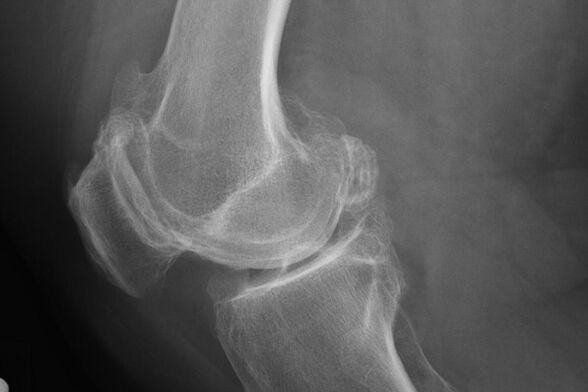

Ang X -ray ay makakatulong na makilala ang mga paglihis sa kartilago.

Matapos ang pagsusuri, inireseta ng doktor ang radiography ng pasyente. Ito ang pangunahing pamamaraan ng pag -diagnose ng arthrosis ng kasukasuan ng tuhod ng anumang degree.

Binibigyan ng X -ray ang doktor ng isang ideya ng mga pagbabagong nagaganap sa kartilago ng kasukasuan. Gayunpaman, sa ilang mga kaso, ang paunang yugto ay maaaring hindi tinukoy sa larawan.

Kung kinakailangan, ang doktor ay maaaring magreseta ng isang paulit-ulit na daanan ng isang x-ray o computed at magnetic resonance tomography.